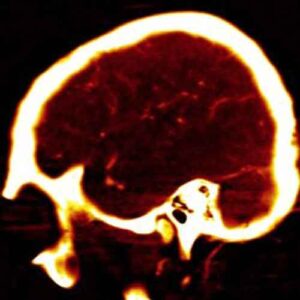

Il fumo, la pressione alta e il colesterolo elevato possono essere fatali per gli individui sopravvissuti ad un emorragia subaracnoidea...

Uno studio mette in luce i pericoli per il cervello: smettere comporta nel tempo una diminuzione del fattore di rischio...